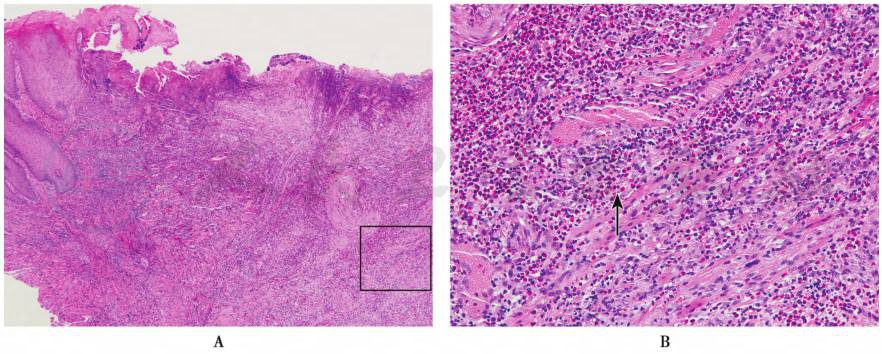

急性溃疡可见明显的假膜,由纤维蛋白渗出及中性粒细胞浸润构成,其边缘上皮轻度增生。溃疡底部为肉芽组织,见毛细血管增生和扩张,混合性炎症细胞浸润。当溃疡开始愈合时,可见边缘上皮开始再生,在纤维蛋白凝固物的下方爬行并逐渐覆盖肉芽组织。慢性溃疡的底部也为炎症肉芽组织,更深层有明显的纤维增生,形成瘢痕;由于持续的创伤或局部细胞因子表达不足,可能不发生上皮再生。嗜酸性溃疡在组织学上类似慢性创伤性溃疡,炎症细胞浸润深而广泛,可达肌层,造成肌组织变性;炎症区成纤维细胞增生,血管内皮细胞肥大,浸润的炎症细胞包括嗜酸性粒细胞、组织细胞、淋巴细胞等,其中嗜酸性粒细胞浸润是其特征性表现(图1)。

图1嗜酸性溃疡

A.表面溃疡,炎症浸润深达肌层 B.图A的局部(方框区)放大,肌束间见大量嗜酸性粒细胞浸润(箭头示)